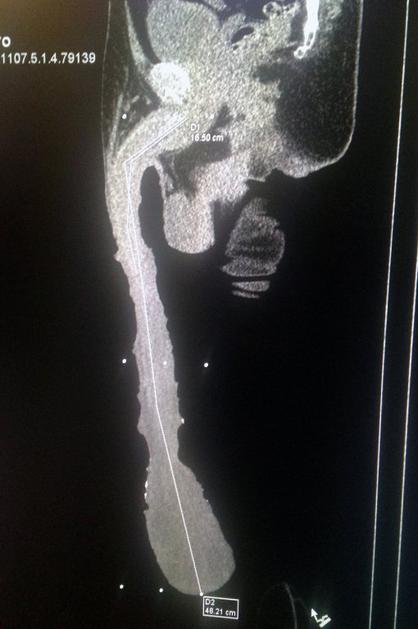

To službo je dobil zaradi svojega 48 cm dolgega penisa